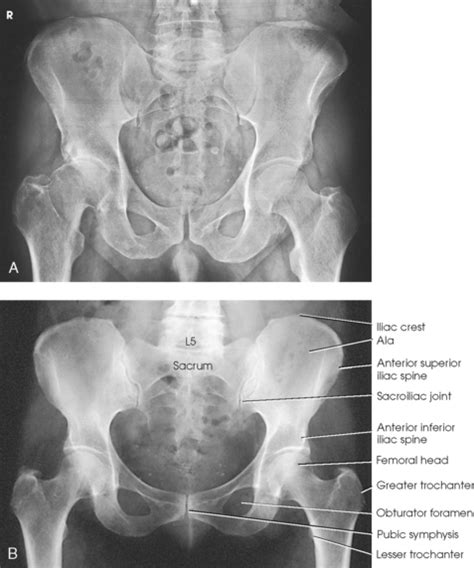

What are bones in the pelvic area? • the bones of male pelvis are heavier, thicker and stronger while the bones of female pelvis are lighter and less dense. Male pelvis has a longer and narrower sacrum whereas female pelvis has wider, shorter, and less curved sacrum. More images for male pelvis vs female pelvis » The pelvic brim (also called pelvic inlet) is.

Human Pelvis, Male and Female | ClipArt ETC from etc.usf.edu In this video you will learn about the following differences between male and female pelvis.structure1.a male pelvis is smaller and narrower while a fema. Which pelvis in the illustration above is the male pelvis? • the bones of male pelvis are heavier, thicker and stronger while the bones of female pelvis are lighter and less dense. The pelvic brim (also called pelvic inlet) is. This causes the sides of the. Male pelvis has a longer and narrower sacrum whereas female pelvis has wider, shorter, and less curved sacrum. What is the difference between male and female pelvis? What are bones in the pelvic area?